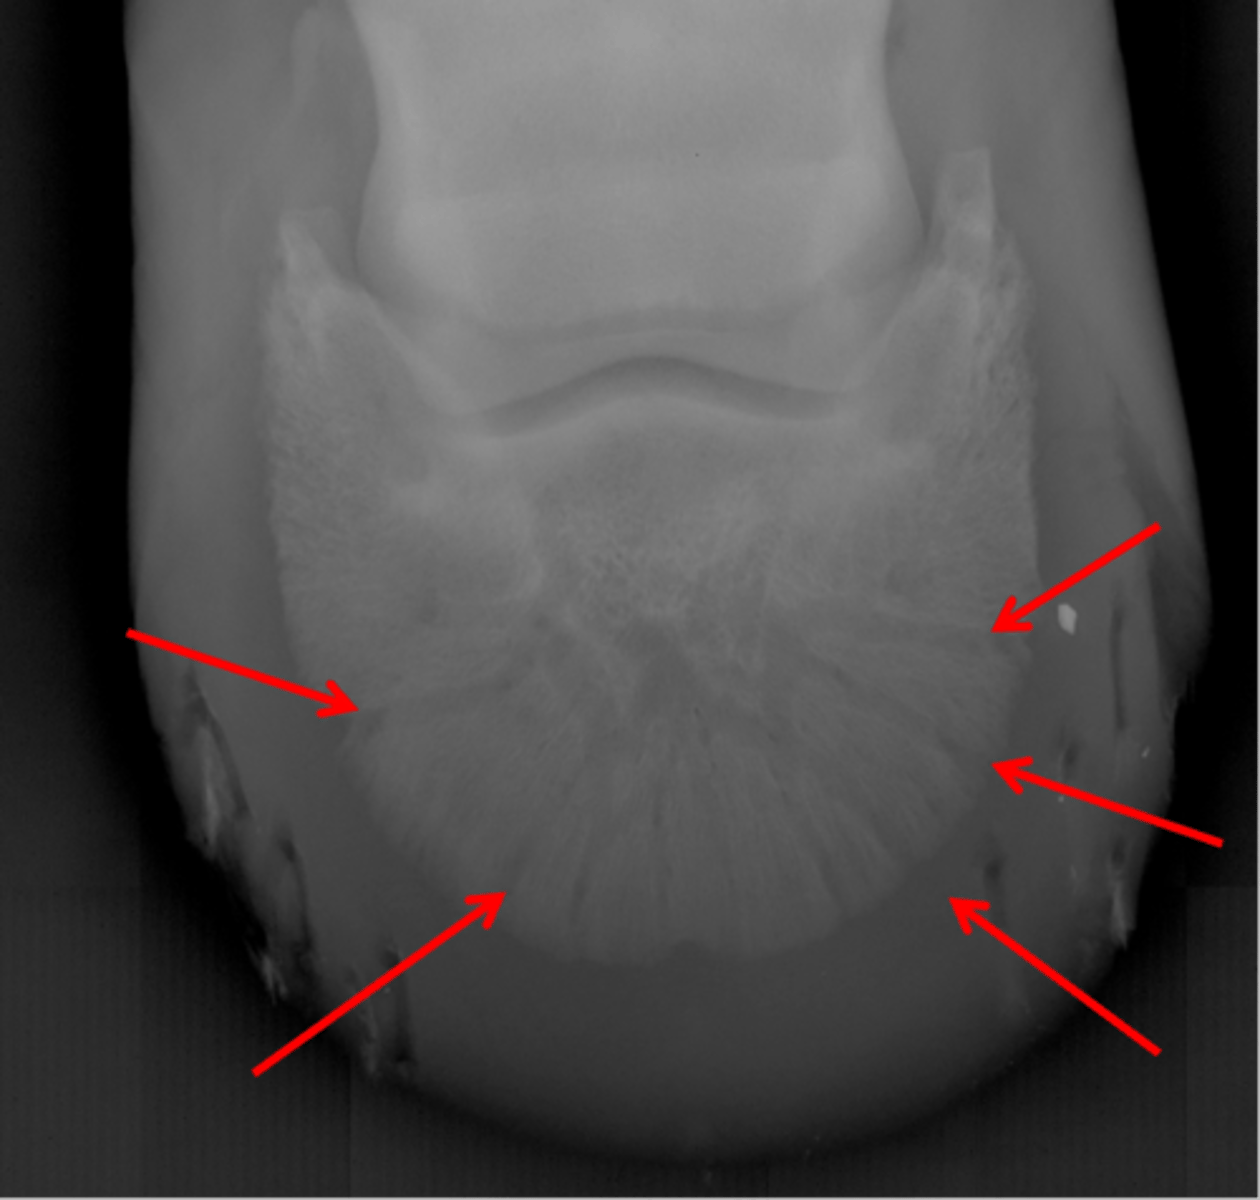

Navicular bone

Articular surface of navicular bone

Flexor surface of navicular bone

Sagittal ridge

Synovial invaginations

Palmar process of P3

Palmar aspect of P2